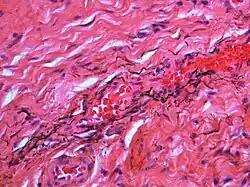

Over time, the amalgam particles embedded in the soft tissues corrode.[5]: 183 Macrophages take up the exogenous particles, and the silver in amalgam leads to staining of collagen fibers.[5]: 183

If necessary, the diagnosis can be confirmed histologically by excisional biopsy, which excludes nevi and melanomas.[3]: 138 If a biopsy is taken, the histopathologic appearance is:[1]

- Pigmented fragments of metal within connective tissue

- Staining of reticulin fibers with silver salts

- A scattered arrangement of large, dark, solid fragments or a fine, black or dark brown granules

- Large particles may be surrounded by chronically inflamed fibrous tissue

- Smaller particles surrounded by more significant inflammation, which may be granulomatous or a mixture of lymphocytes and plasma cells